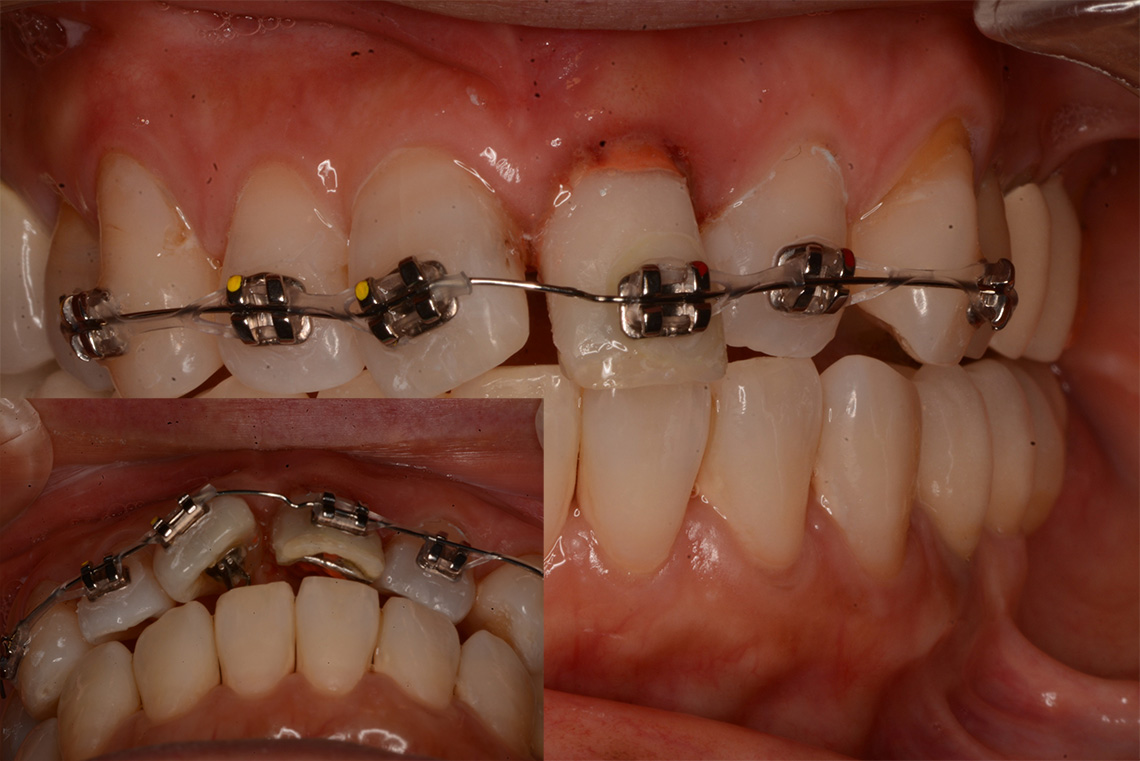

歯根を牽引

改めて矯正線での部分矯正を行う